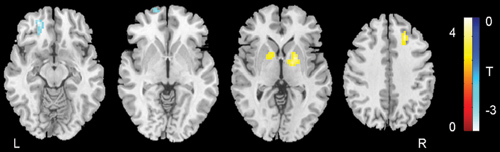

The results showed that the patients with ADHD had altered structure and function located in areas of the brain like the orbitofrontal cortex, which is primarily involved in the cognitive processing of strategic planning, and the globus pallidus, which is involved in executive inhibitory control.

The researchers also found abnormalities in the connections between resting-state brain networks associated with executive dysfunction. These abnormalities indicate more widespread brain alterations in ADHD than previously had been shown, Gong said.